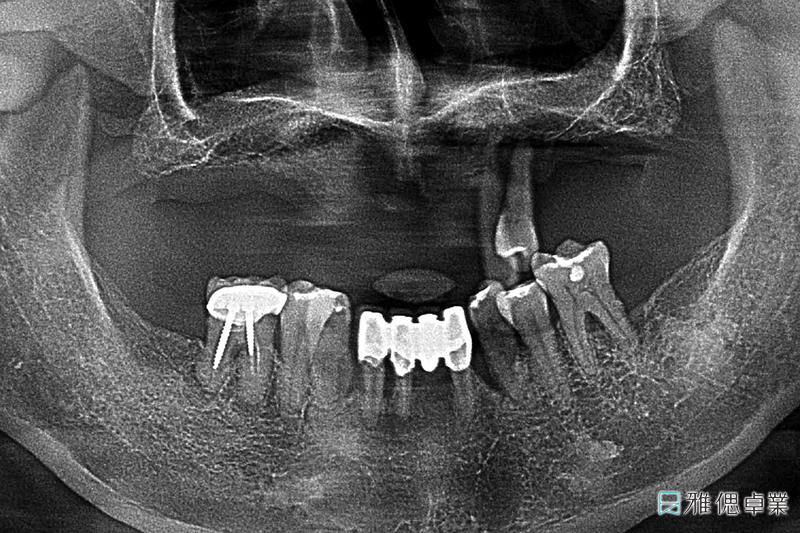

術前環口X光片,上顎只剩下2顆牙齒,下顎也有牙周、排列、咬合等問題

治療過程中的環口X光片

最終完成的環口X光片